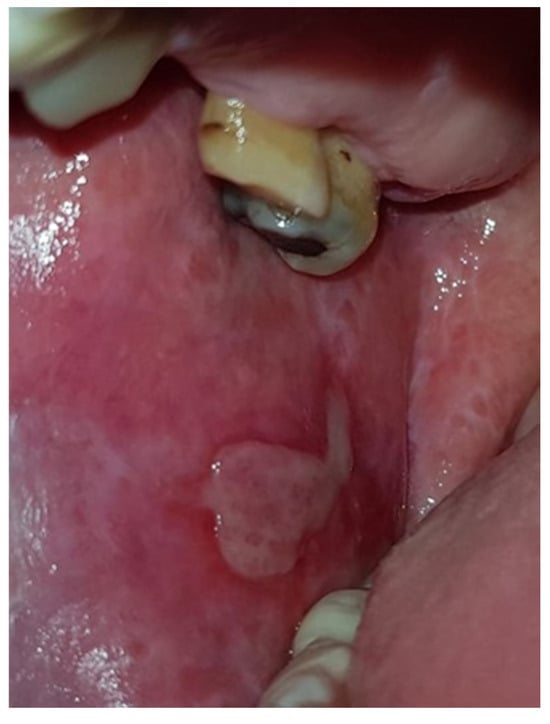

| Bullous/Erosive (Mixed) | 36 (19.4%) | 23 (17.7%) | 13 (23.2%) | 0.3838 | 8 (17.0%) | 28 (20.1%) | 0.6417 | 5 (16.7%) | 25 (19.1%) | 6 (24.0%) | 0.7825 |

| Atrophic | 13 (7.0%) | 11 (8.5%) | 2 (3.6%) | 0.2303 | 3 (6.4%) | 10 (7.2%) | 0.8526 | 1 (3.3%) | 10 (7.7%) | 2 (8.0%) | 0.6908 |

| Plaque-like | 4 (2.2%) | 2 (1.5%) | 2 (3.6%) | 0.3631 | 1 (2.1%) | 3 (2.2%) | 0.9676 | 1 (3.3%) | 2 (1.5%) | 1 (4.0%) | 0.6544 |